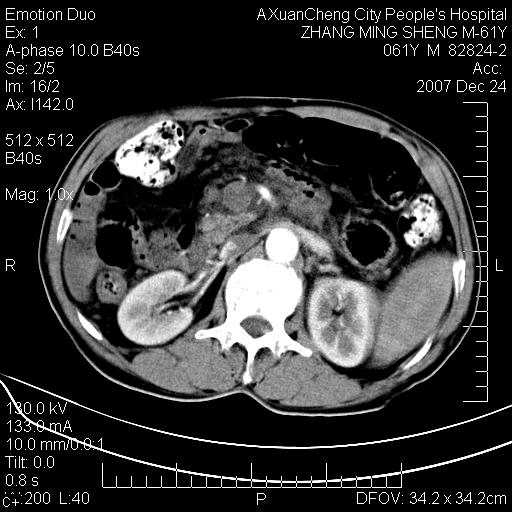

标题: CT11031:M61Y,胰腺占位

大家侃侃门静脉和胆管系统怎么回事,肝内转移?

胰腺癌肝转移

2,肝内多发结节状低密度占位,伴门脉及肠系膜上v栓子形成.考虑a;门脉及肠系膜上v血栓后肝改变.b;弥漫型肝癌伴门脉及肠系膜癌栓.

肝硬化,门脉高压,脾肿大;弥漫性肝癌,肝内、门脉、腹膜后淋巴结转移,肝内外胆管扩张,胰头区占位,建议mr检查

胰腺癌伴肝内转移;门脉、肠系膜上v癌栓形成。

考虑为:胰腺癌伴肝脏转移、腹膜后淋巴结转移,门静脉及肠系膜上静脉瘤栓形成。

胰体尾癌伴肝内转移,门静脉及肠系膜上静脉瘤栓形成.